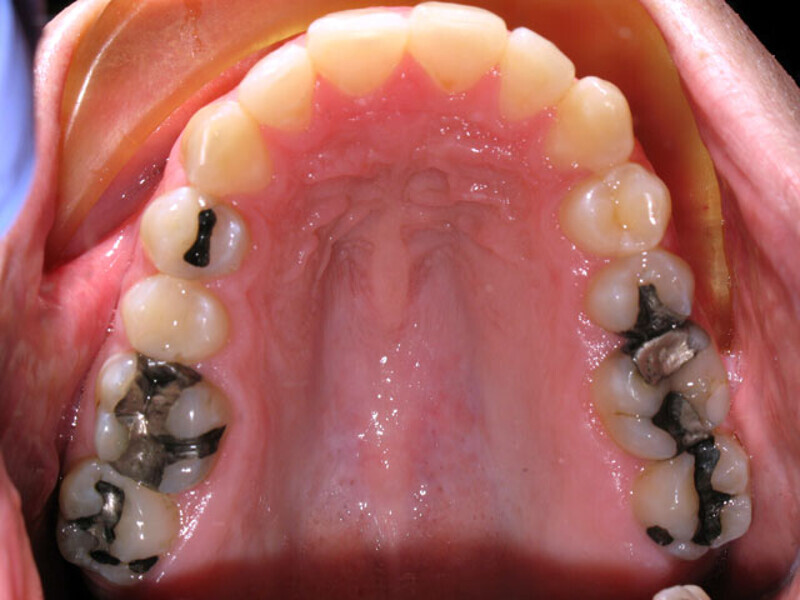

ClearCorrect treatment of crowding